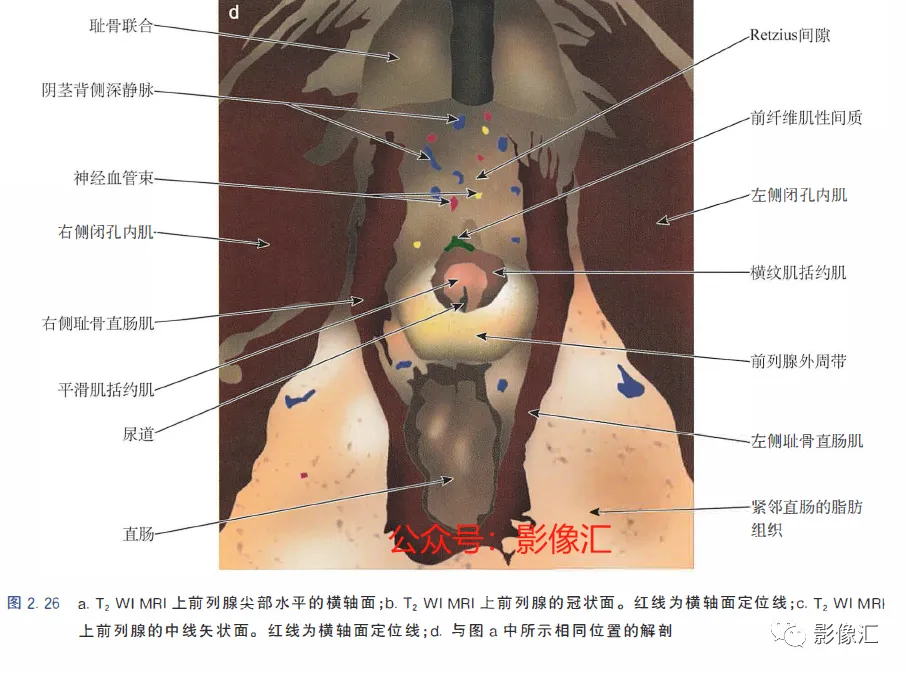

8. 前列腺尖部的横轴面(图2.26)